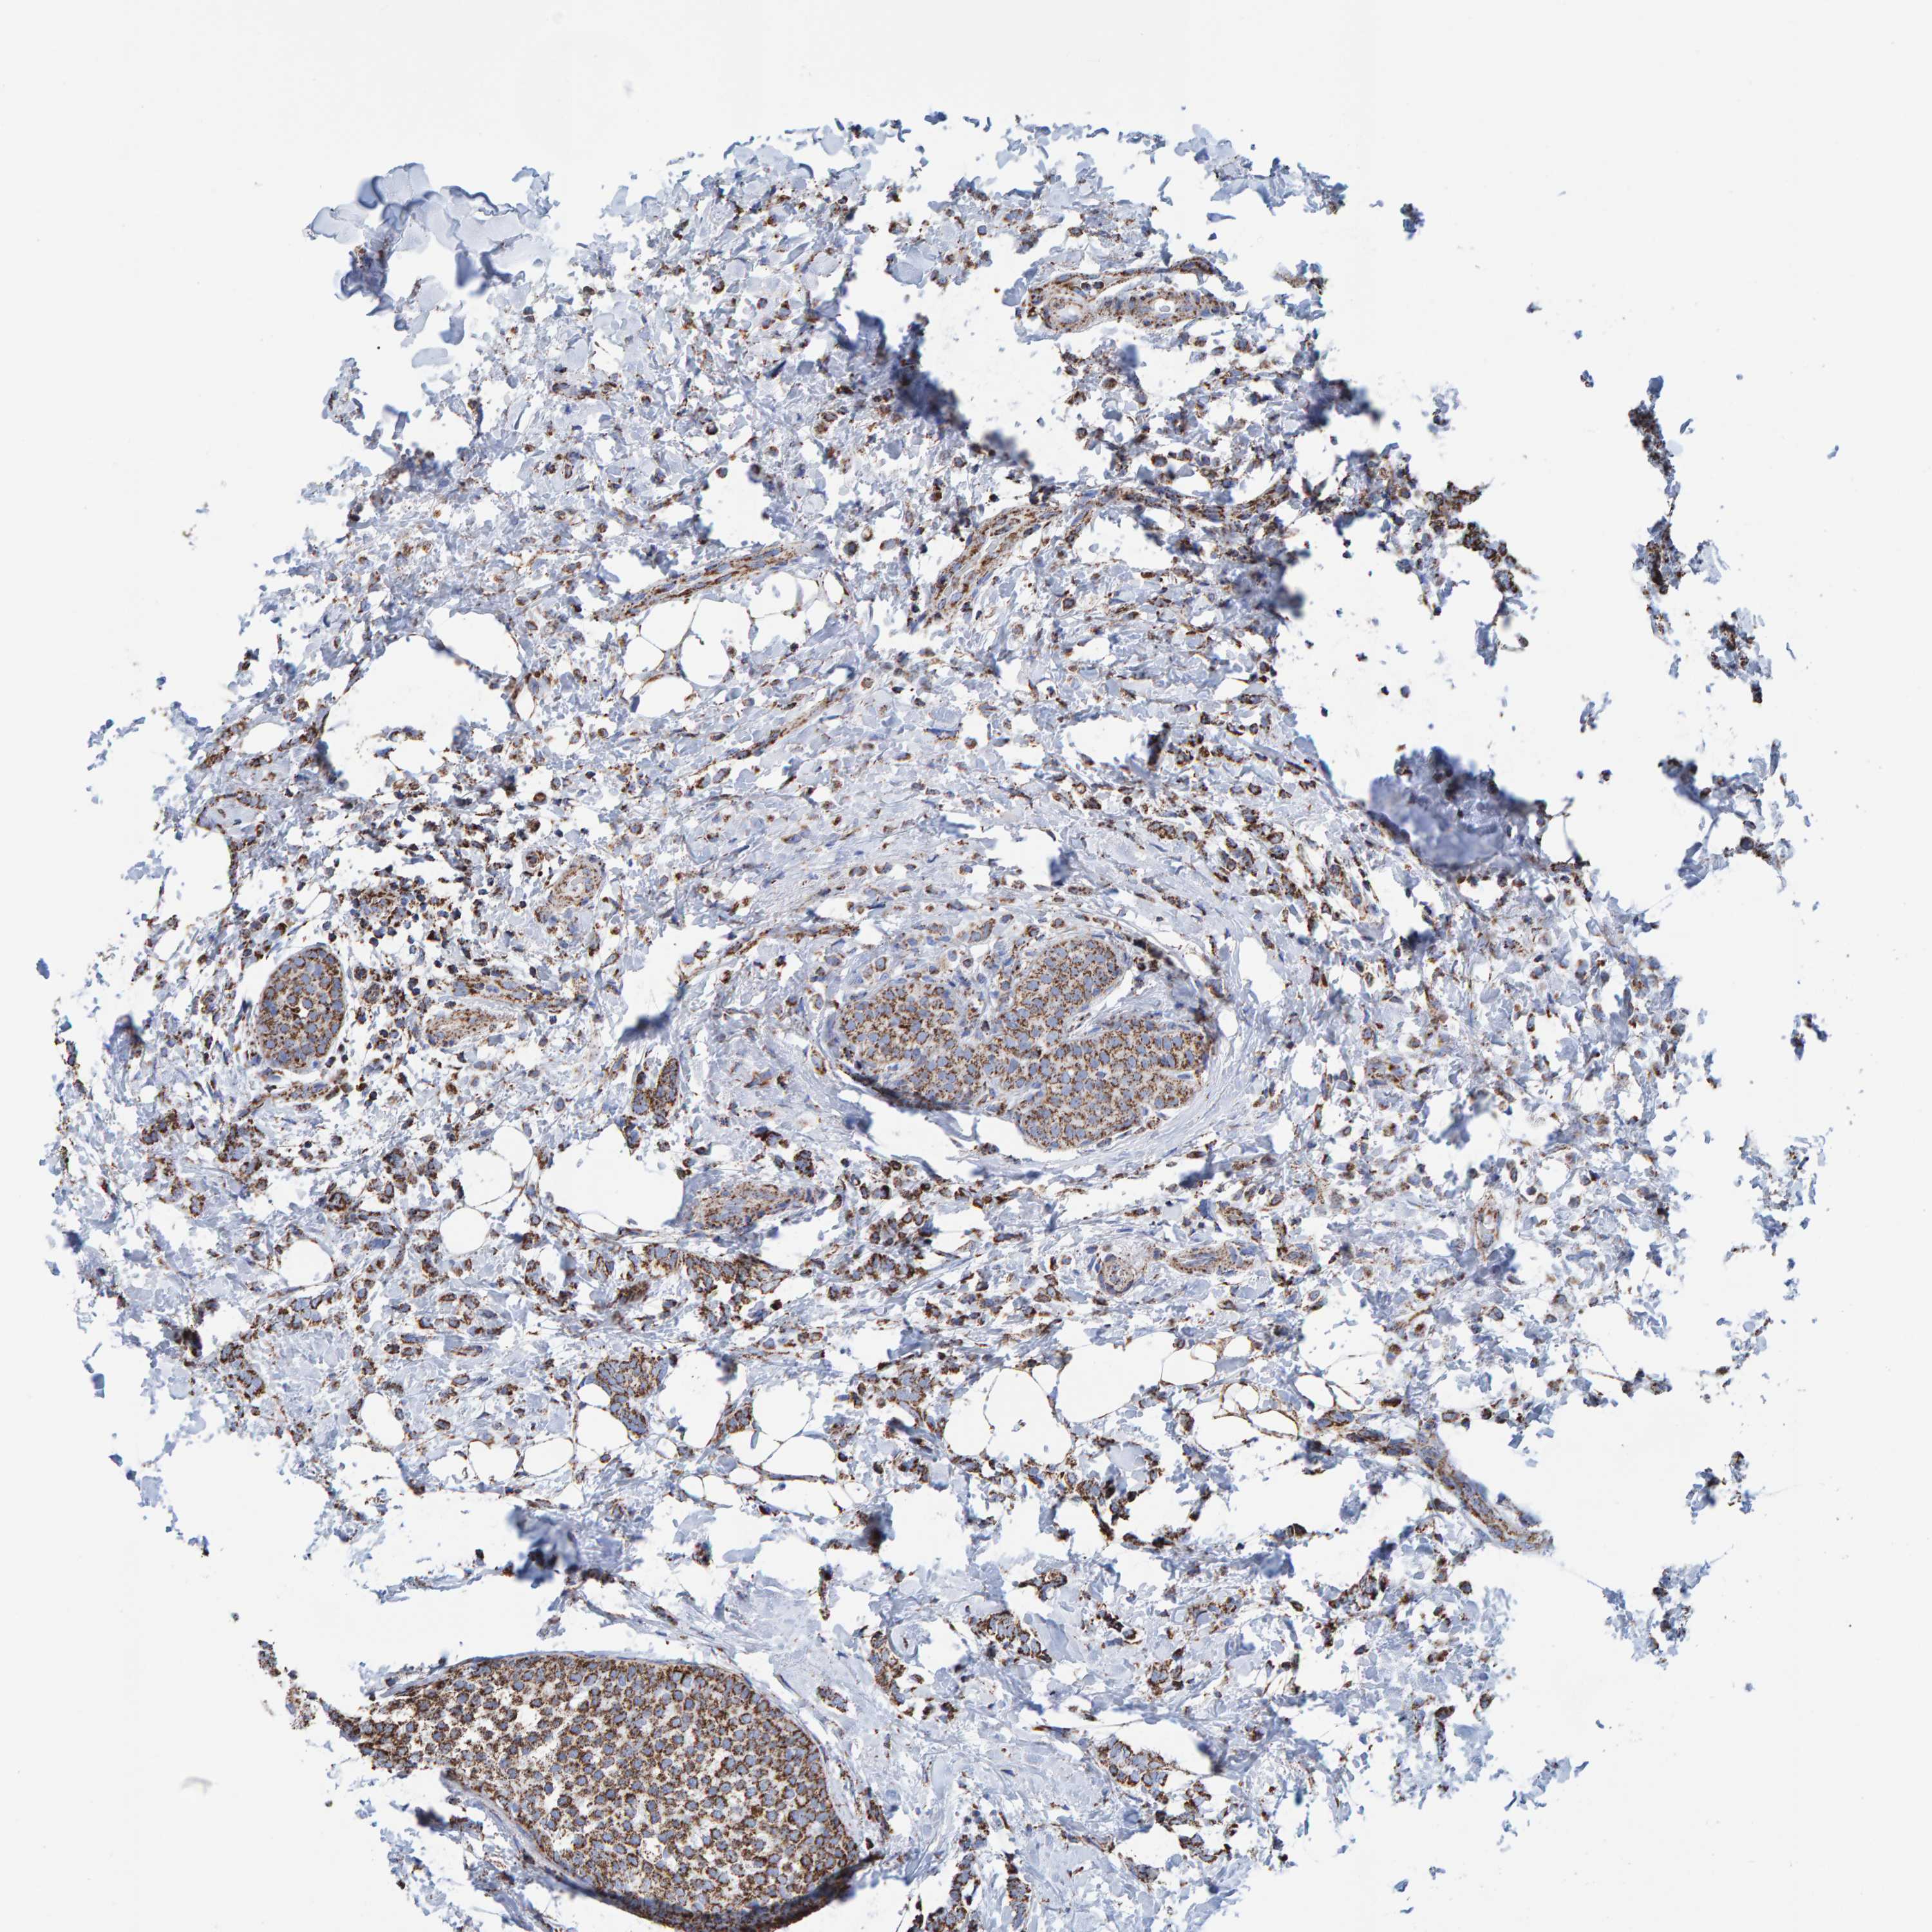

CANCER BREAST CANCER Show tissue menu

BRCA TCGA BRCA VALIDATION PROTEIN EXPRESSION